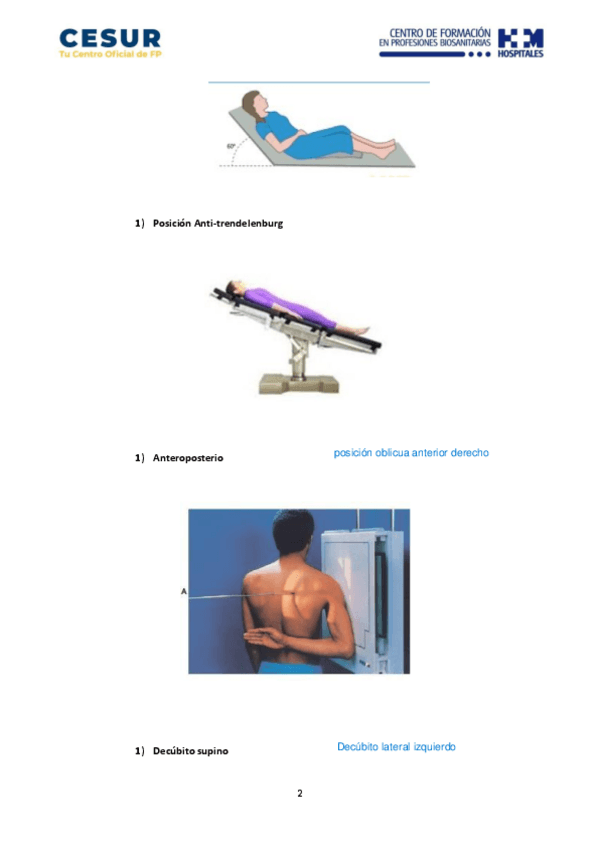

He publicado nuevos apuntes de Anatomía por la Imagen: Ejercicios-Tema-2-API-1-1.pdf